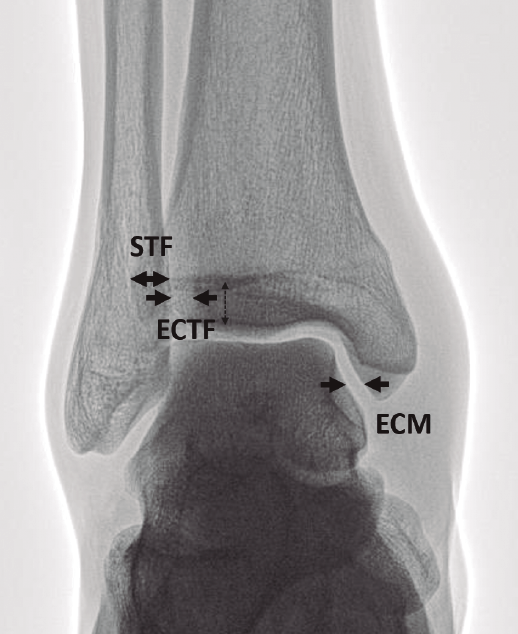

En su artículo de 1989, Harper y Keller(11) establecieron los criterios radiográficos de una sindesmosis estable (Figura 1):

- Espacio claro tibiofibular (ECTF): distancia horizontal entre el borde lateral del maléolo posterior y el borde medial del peroné menor de 6 mm, tanto en la proyección AP como en la de mortaja.

- Solapamiento tibiofibular (STF): distancia entre el borde medial del peroné y el borde lateral del tubérculo tibial anterior mayor de 6 mm, un 42% del ancho del peroné en la proyección AP o mayor de 1 mm en la proyección de mortaja.

Las medidas son tomadas a 1 cm proximal del espacio articular del tobillo. - Espacio claro medial (ECM) ha sido otro parámetro habitualmente usado. Es la distancia entre el aspecto lateral del maléolo medial y el borde medial del astrágalo menor de 4 mm(12).

Figura 1. Parámetros radiográficos clásicos de sindesmosis estable en proyección anteroposterior (AP). ECM: espacio claro medial menor de 4 mm; ECTF: espacio claro tibiofifular menor de 6 mm; STF: solapamiento tibiofibular mayor de 6 mm.